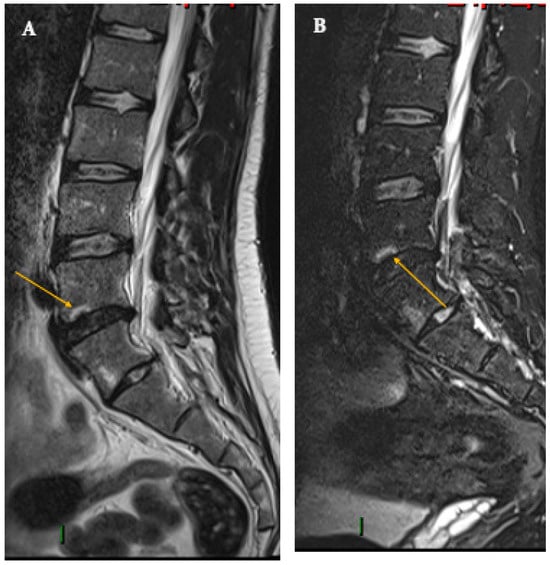

4. Imaging Features of Spondylodiscitis of Bacterial Origin

5. Tuberculous Origin (Pott’s Disease)